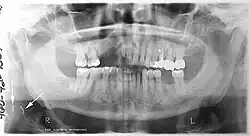

Panoramic radiograph

A dental panoramic radiograph, showing the maxilla and mandible, all the teeth including the "wisdom teeth," the frontal and maxillary sinuses, the nasal cavity and the temporomandibular joint and other near by head and neck anatomy. | |

A panoramic radiograph is a panoramic scanning dental X-ray of the upper and lower jaw. It shows a two-dimensional view of a half-circle from ear to ear. Panoramic radiography is a form of focal plane tomography; thus, images of multiple planes are taken to make up the composite panoramic image, where the maxilla and mandible are in the focal trough and the structures that are superficial and deep to the trough are blurred.